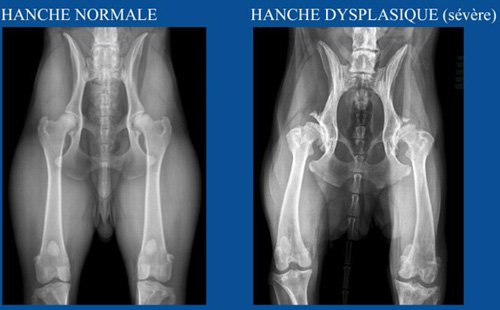

LE DEPISTAGE DE LA DYSPLASIE

5 Niveaux sont possibles : HD-A / HD-B / HD-C / HD-D / HD-E.

Ne sont considérés comme Hors Dysplasie que HD-A et HD-B.